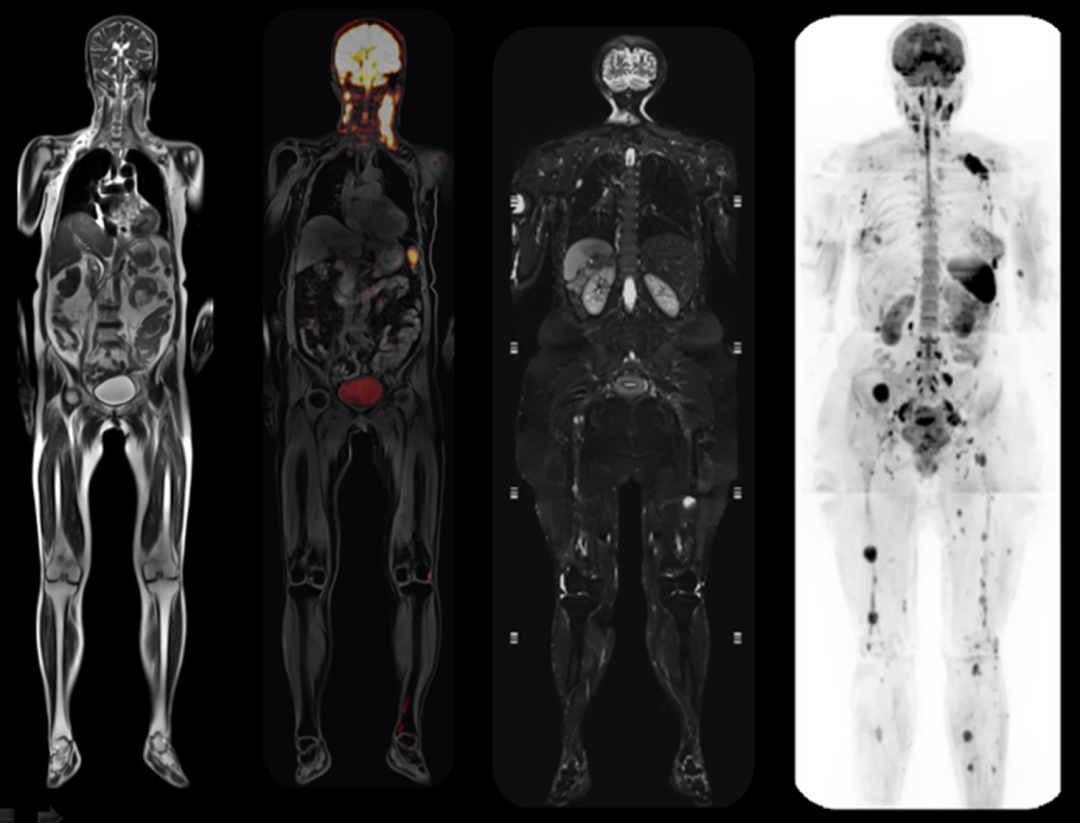

高清功能成像平台

MAGNETOM Vida对于磁体、梯度、射频及线圈系统的控制精度比传统磁共振提高了整整一个数量级,可以稳定使用多次激发、分段读出等技术,从根本上突破了弥散信号衰减过快导致的弥散图像分辨率无法提高的限制,让弥散图像质量达到常规解剖成像一样水平,而且实现横断位、矢状位和冠状位等多平面的成像。

磁共振矩阵怎么计算【重磅】新一代智慧型生命感知磁共振——MAGNETOM Vida, 成功落户中大放射并全面投入使用!!!_https://www.jmylbn.com_新闻资讯_第17张

全身MR

大范围弥散成像时,Vida独有的生命矩阵层面匀场技术,可对每层弥散扫描进行单独匀场,进一步保证弥散成像质量